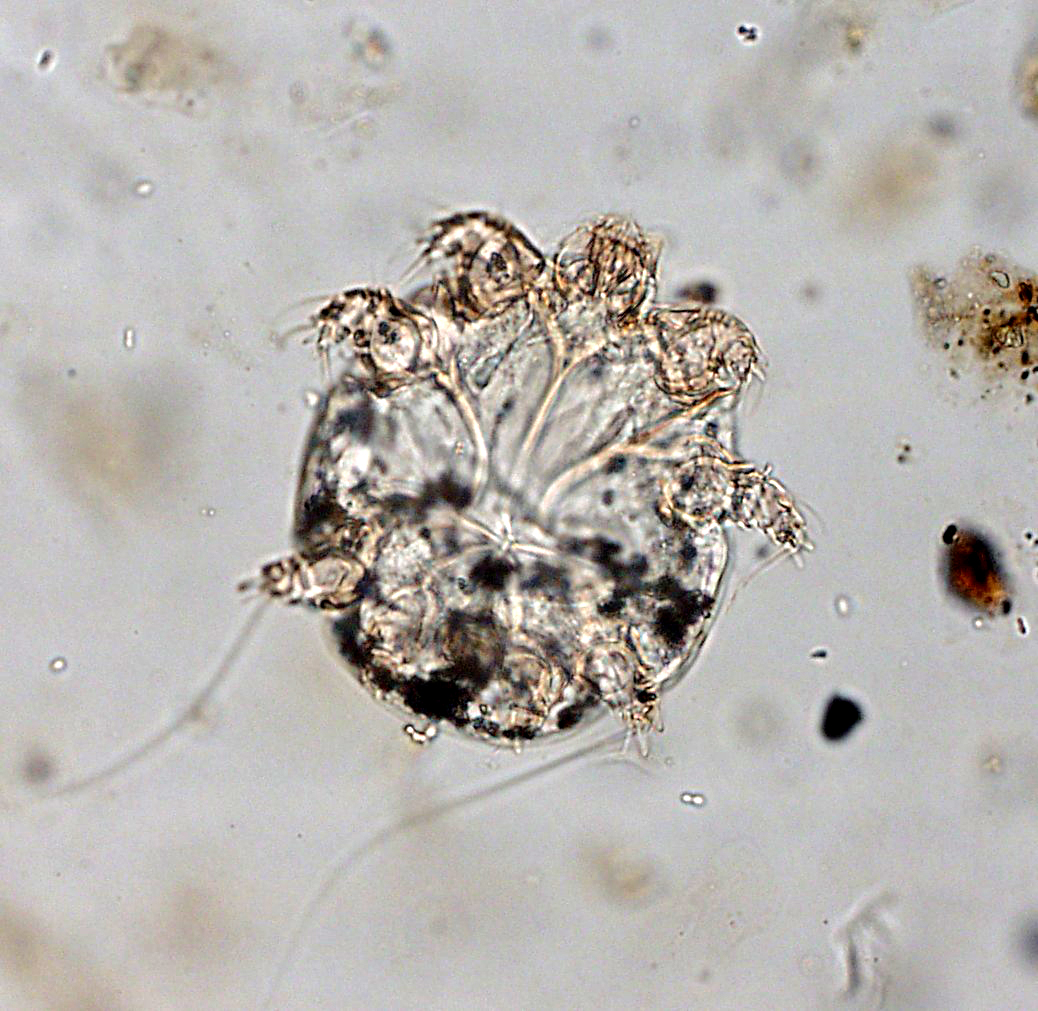

- Увидеть зудневых клещей можно только через увеличение микроскопа, а первые симптомы заболевания могут появиться спустя две недели после заражения;

Sarcoptes scabiei в своем жизненном цикле проходит четыре стадии: яйцо, личинка, нимфа и имаго. Самки откладывают 2-3 яйца в день, зарываясь под кожу. Яйца овальные, длиной от 0,10 до 0,15 мм, вылупляются через 3-4 дня. После вылупления яиц личинки мигрируют на поверхность кожи и зарываются в неповрежденный роговой слой, чтобы построить почти невидимые короткие ходы, называемые мешочками для линьки. Личиночная стадия, которая выходит из яиц, имеет только 3 пары ног и длится от 3 до 4 дней. После линьки личинок у образовавшихся нимф 4 пары ног. Эта форма линяет в несколько более крупных нимф, прежде чем превратиться во взрослых особей. Личинки и нимфы часто можно найти в мешочках для линьки или в волосяных фолликулах, и они похожи на взрослых особей, только меньше. Взрослые особи — круглые, мешкообразные безглазые клещи. Самки имеют длину от 0,30 до 0,45 мм и ширину от 0,25 до 0,35 мм, а самцы чуть больше половины этого размера.![]()